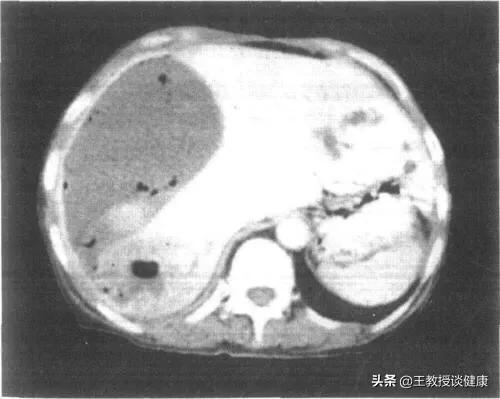

CT检查所见肝右叶肝脓肿影像

CT所见肝右叶肝脓肿明显液化影像

下面CT图示就是肝脓肿部位。